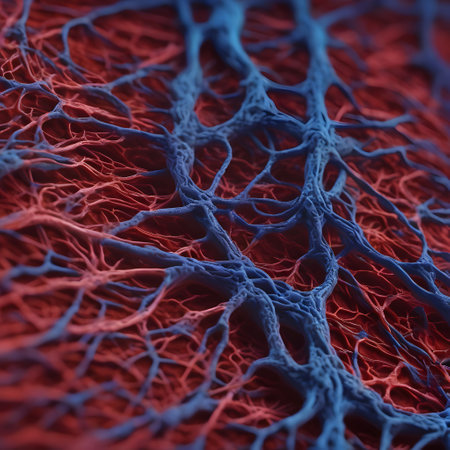

Macro view of human blood vessel network with red and blue tones showing capillaries and vein structure, ideal for illustrating medical anatomy and biology research.

Detailed visuals showcase the complex network of blood vessels in human anatomy.

abstract of blood vessels as glowing fractals. Generative AI

A detailed view of red blood vessels intertwines across a soft gradient background. The intricate network showcases the complexity of human circulation highlighting the various sizes and shapes of the vessels

Vessel flow texture in red and blue lighting showing microscopic circulation system pattern symbolizing human biology, anatomy, and healthcare science visualization.

Detailed visualization of intertwined red capillaries resembling a biological network, set against a dark blue backdrop